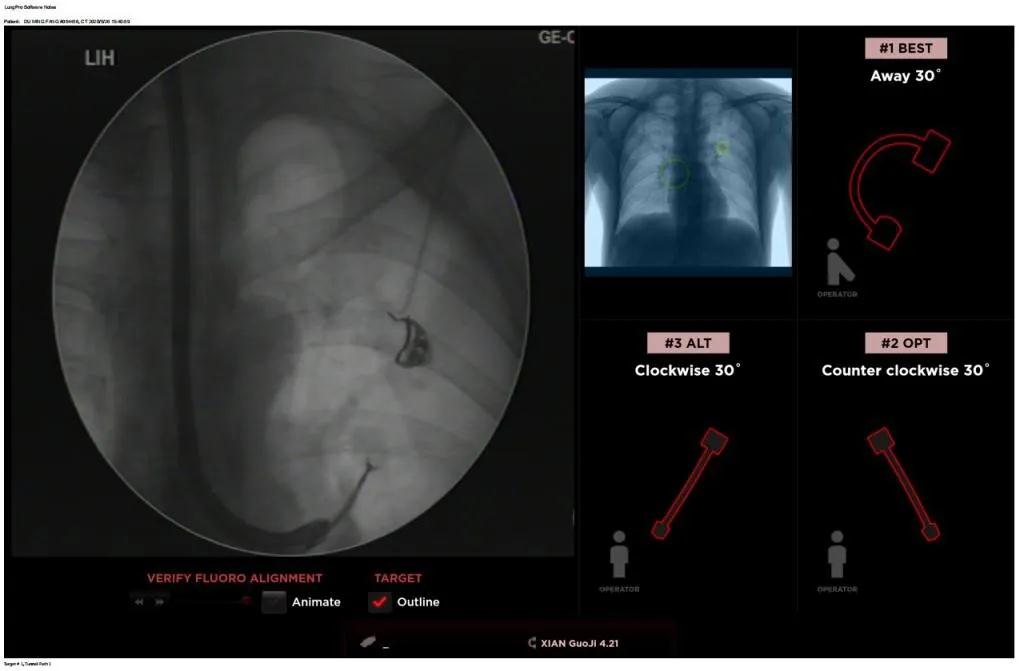

西安國際醫(yī)學(xué)中心醫(yī)院呼吸內(nèi)科完成西北地區(qū)首例LungPro全肺導(dǎo)航系統(tǒng)引導(dǎo)下BTPNA手術(shù)

近日,西安國際醫(yī)學(xué)中心醫(yī)院胸科醫(yī)院歐陽海峰副院長完成西北地區(qū)首例LungPro全肺導(dǎo)航系統(tǒng)引導(dǎo)下經(jīng)支氣管鏡跨肺實(shí)質(zhì)肺外周結(jié)節(jié)活檢術(shù)。

經(jīng)過充分的討論后,歐陽海峰副院長決定為患者實(shí)施LungPro全肺導(dǎo)航系統(tǒng)引導(dǎo)的經(jīng)支氣管跨肺實(shí)質(zhì)肺外周結(jié)節(jié)活檢術(shù)。Broncus導(dǎo)航系統(tǒng)LungPro具有全球領(lǐng)先獨(dú)創(chuàng)的BTPNA技術(shù)(支氣管鏡下跨結(jié)節(jié)抵達(dá)術(shù)),可以實(shí)現(xiàn)對氣道外周孤立性肺小結(jié)節(jié)的精準(zhǔn)定位,建立直接通往氣道外病變部位的通道,以實(shí)現(xiàn)全肺的診斷及后續(xù)治療。這項(xiàng)技術(shù)不僅彌補(bǔ)了現(xiàn)有支氣管鏡技術(shù)由于受限于病變部位是否有氣道可通向以及無法準(zhǔn)確定位病變部位而造成的較低診斷率,同時還彌補(bǔ)了CT引導(dǎo)下經(jīng)胸穿刺(TTNA)無法適用于某些特定部位如中央及肩胛骨等結(jié)節(jié)的問題,并且還避免了經(jīng)胸穿刺給患者帶來氣胸、出血的高風(fēng)險(xiǎn),可有效提高肺部結(jié)節(jié)及早期肺癌診斷陽性率,亦可用于早期肺癌的射頻消融或微波治療,具有微創(chuàng)、安全、同期雙肺診療等優(yōu)勢。

BTPNA技術(shù)整合了虛擬導(dǎo)航支氣管鏡VBN、氣道內(nèi)超聲rEBUS、TBNA、高壓球囊擴(kuò)張、X線輔助等多項(xiàng)三、四級呼吸內(nèi)鏡技術(shù)。歐陽海峰副院長有3000 TBNA、1000 rEBUS、500 VBN、800 球囊擴(kuò)張方面的技術(shù)積累,10年來個人每年完成三、四級呼吸內(nèi)鏡手術(shù)1200余例,這有效保障了BTPNA技術(shù)的順利開展。

團(tuán)隊(duì)術(shù)前進(jìn)行了精心的準(zhǔn)備,通過高分辨率CT建立了導(dǎo)航路徑,在麻醉科手術(shù)室的配合下,借助LungPro引導(dǎo)順利的確定了病灶部位、建立隧道并實(shí)施活檢,術(shù)后患者恢復(fù)順利出院。